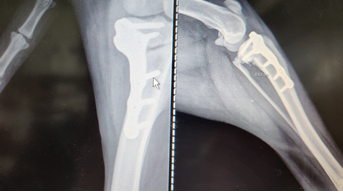

Contamos con modernos equipos que forman uno de los principales medios para realizar un diagnóstico seguro para detectar patologías.

Contamos con el servicio de cirugías como tratamiento necesario para tratar patologías. Por eso nuestros médicos están altamente preparados y nuestra área de quirófano cuenta con los equipos, tecnología y protocolos indispensables.